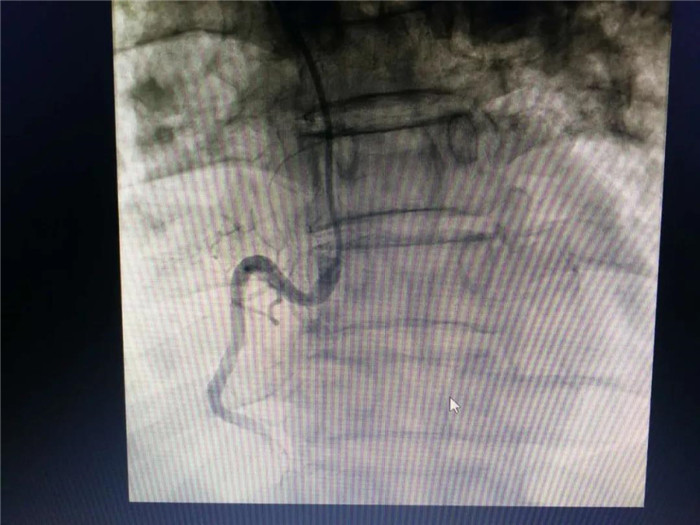

10月25日,庐江县中医院心血管内科团队成功开展首例急性心肌梗死急诊冠脉造影+冠状动脉支架植入术。患者为老年男性,因反复心慌胸闷2月,加重7小时入住我院心血管科。心电图示:下壁心肌梗死,肌钙蛋白阳性,心肌标志物升高,心室率80次/分;结合病史考虑冠心病,急性心肌梗死。

心血管内科团队仔细分析患者病情,严格评估,精心制定了合理的治疗方案。10月25日,在DSA下,行急性心肌梗死介入手术,术中抽出了血栓,打通了血管,手术时间50分。手术非常成功,术后患者恢复良好。